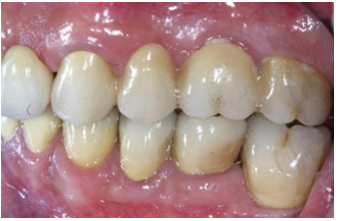

Figure 24: Left side view of final restorations (one year recall).

In order to optimize final aesthetics the 5 mandibular anteriors were prepared for all ceramic restorations. Four all ceramic veneers (E-max Ivoclar Co, Liechtenstein) and an all ceramic crown (#42) completed the final restorations. A final occlusal splint was also fabricated chairside (prior to the final cementation of ceramic veneers) for the protection of final restoration and control of TMJ function (Figure 19,20). Minimal occlusal modifications of the splint were necessary after final cementation of mandibular anteriors. The final radiographic examination was kept as a record for future re-examinations (Figure 21). Finally, the patient was enrolled to a 3 months recall program. In each recall and maintenance visit, the periodontal tissues, the abutments and the stomatognathic system were thoroughly examined, preventive regimens were applied and patient compliance was assessed. Two years later, the excellent periodontal condition and performance of the restoration was registrated (Figure 22-24). The patient complied with proper oral hygiene, reduced smoking and adopted a regular use of the occlusal splint. Strict recall and maintenance visits were necessary for long term success of this full mouth rehabilitation. The patient stopped smoking immediately after 6 months and changed nutritional habits in order to eliminate secondary caries.